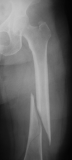

X-ray of right hip osteoporosis, age 54